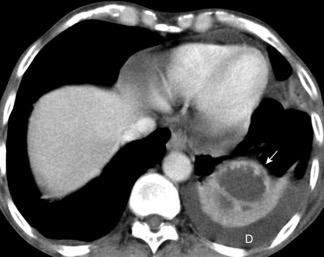

39. EMPIEMA DE ORIGEN SUBDIAFRAGMÁTICO

40. EMPIEMA PLEURAL. ORIGEN HEPÁTICO